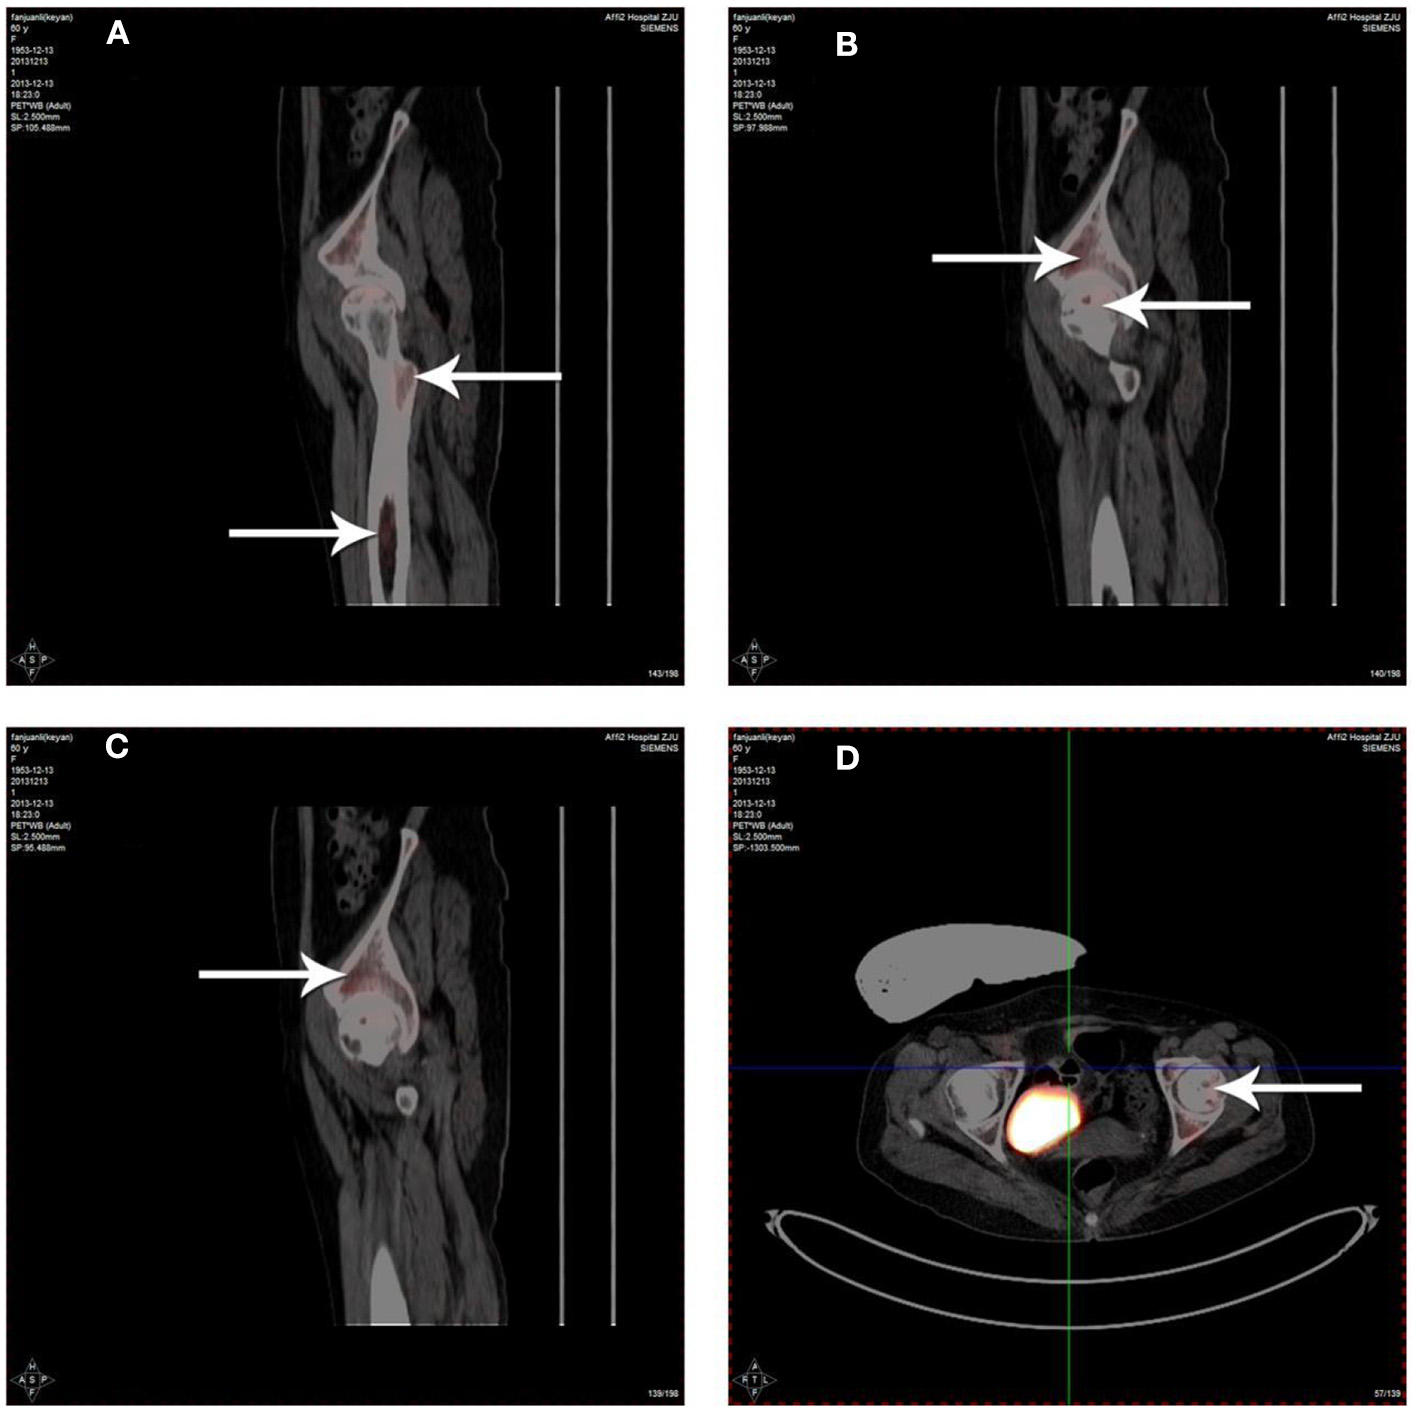

Radioactivity of 18F-FDG was detected in the femoral bone marrow cavity (Figure 3A), necrotic area of the femoral head (Figures 3B,D) and acetabulum (Figure 3C) by 3D-PET imaging after PBSCs transplantation via the medial circumflex femoral artery. The data showed that although PBSCs labeled with 18F-FDG were widely distributed around the hip, such as femoral bone marrow cavity, femoral head and acetabulum, PBSCs were generally located in necrotic area of the femoral head. These revealed that PBSCs could enter into the femoral head through the medial circumflex femoral artery and migrate into the necrotic field of the femoral head after intra-arterial infusion.

Figure 3

Distribution of 18F-FDG labeled PBSCs after infusion via the medial circumflex femoral artery. The 18F-FDG labeled PBSCs could be observed in the femoral bone marrow cavity (A), necrotic area of the femoral head (B,D) and acetabulum (C). The 18F-FDG labeled PBSCs could be seen in necrotic area of the femoral head indicating that PBSCs could enter into the femoral head and migrate into necrotic field of the femoral head participating in the repair of osteonecrosis after infusion through the medial circumflex femoral artery.